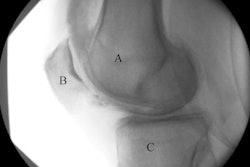

A knee joint of a patient on imaging shows (A) severe cartilage defects and (B) an intact knee joint. Images and caption courtesy of RSNA.The team found significant ties between corticosteroid injection and postinjection progression of whole-organ MRI scores over two years for the knee overall, lateral meniscus, lateral cartilage, and medial cartilage.